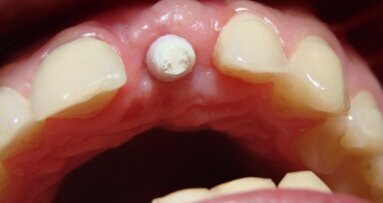

Po upływie 22 miesięcy od wykonania finalnej rekonstrukcji protetycznej doszło do poprzecznego pęknięcia korzenia zęba #12. Podjęto decyzję o natychmiastowej implantacji w tym miejscu. Wybrano poddziąsłowy protokół gojenia. Pacjentka nie wyraziła zgody na wykonanie przeszczepu łącznotkankowego celem zwiększenia objętości dziąsła związanego w okolicy przyszyjkowej implantu.

Ryciny pokazują sytuację po odsłonięciu implantu i 2-tygodniowym okresie gojenia z wykorzystaniem śruby gojącej. Na implancie wykonano koronę tymczasową z kompozytu, co umożliwiło jej łatwą modyfikację w gabinecie. Stwierdzono prawie 2 mm recesję dziąsła oraz brak brodawek dziąsłowych przy zębach sąsiednich.

Na rycinach przedstawiono sytuację kliniczną w 18 miesięcy po wykonaniu implantacji – widoczne są w pełni uformowane brodawki dziąsłowe wokół implantu.